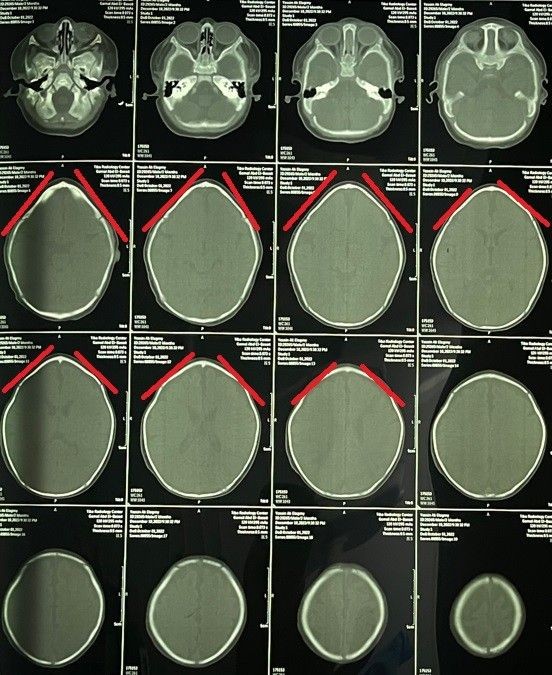

تم إجراء جراحة تقويم ناجحة لطفل يبلغ من العمر شهرين كان يعاني من حالة تعرف باسم "الرأس المثلث". هذا النوع من التشوهات الجمجمية يؤدي إلى ظهور الرأس بشكل مثلثي مع وجود نتوء بارز في الجبهة. الهدف من الجراحة كان تصحيح شكل الجمجمة لضمان النمو الطبيعي للدماغ وحماية الطفل من المشاكل المستقبلية.

• تخطيط دقيق مسبق باستخدام التصوير ثلاثي الأبعاد